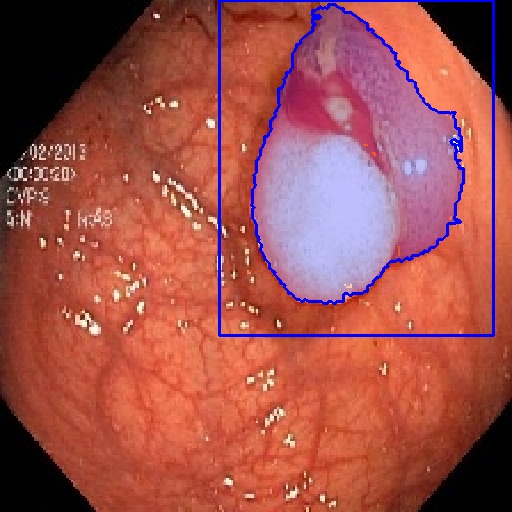

| Fine-Tuning | KvaSir [68] | 2D Endoscope | 1000 |

In 3D settings, we segment 2D slices and merge results for a 3D volume. We also benchmarked with 3D self-supervised methods from [86]. Tables (2) and (3) show that our two versions with ResNet-50 and Sam’s ViT hold the best records in each category. For instance, we outperform 2D SSL methods trained on the same dataset, surpassing foundation models such as SAM, Flava, and Clip. In the prompt-based settings, LVM-Med also delivers better performance compared with SAM. Second, LVM-Med achieves the best overall results on seven of eight segmentation tasks, mostly held by LVM-Med with ResNet-50. The improvement gaps vary on each dataset, for e.g., from on Kvasir and BUID compared with 2D supervised methods.